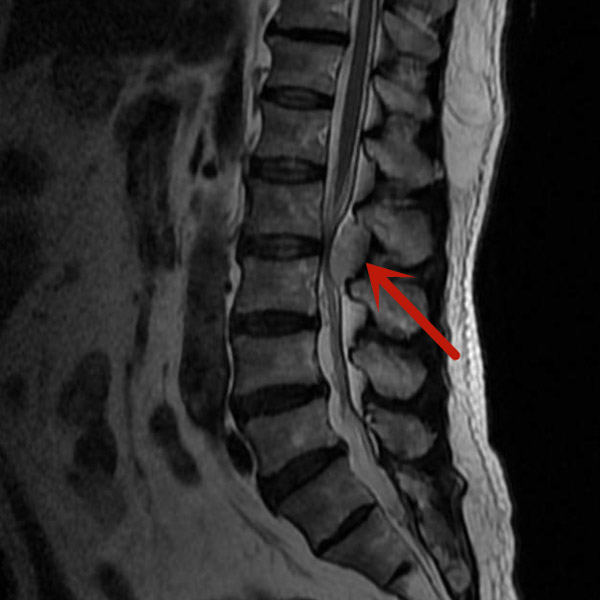

梁先生因双下肢麻木来我院就诊,经磁共振检查发现是腰椎管内血管瘤在作怪,若不及时手术治疗,随着肿瘤的生长、神经长时间受压,将可能导致双下肢瘫痪、大小便失禁等严重后果。

经我院脊柱外科医疗团队研究后,决定对梁先生实施内镜下腰椎管内肿瘤切除术,肿瘤约3.5cm×1.5cm大小,别看肿瘤不大,但要完全通过0.8cm大小切口在内镜下切除,肿瘤后方的椎板切除减压、肿瘤与周围神经的分离、肿瘤的暴露、肿瘤的彻底切除,这都需要娴熟的内镜操作技术。

在完善术前检查,排除手术禁忌,充分做好术前准备后,由微创手术经验丰富的医师主刀,经过两个小时,完整将肿瘤切除。梁先生术后第一天便可下床活动,四天后即康复出院。